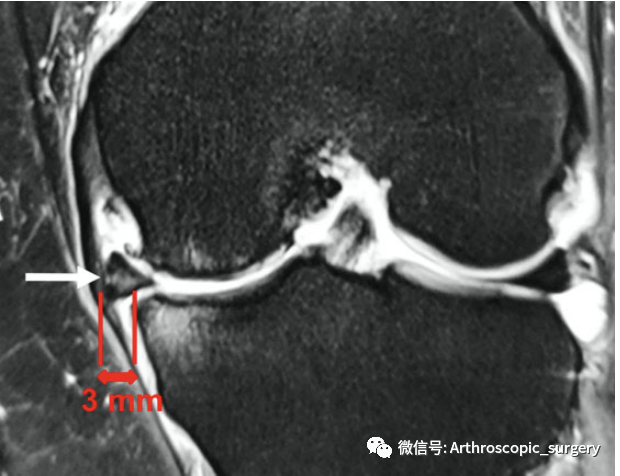

Costa等第一个提出在核磁共振的影像基础上将半月板外凸分为2个亚组:<3mm的被定义为轻微外凸;≥3mm的被定义为严重外凸。虽然后续有不同的学者,根据半月板的解剖特点、在不同状态下的活动情况等等,进行了相应的划分,但是目前大家都比较倾向于采取3mm作为一个分界线,来评价是否存在半月板的外凸。毕竟在一项健康志愿者进行的单独研究发现:半月板平均内侧外凸2.7mm,外侧外凸1.8mm。

冠状位MRI扫描显示半月板外凸3mm(白色箭头)。